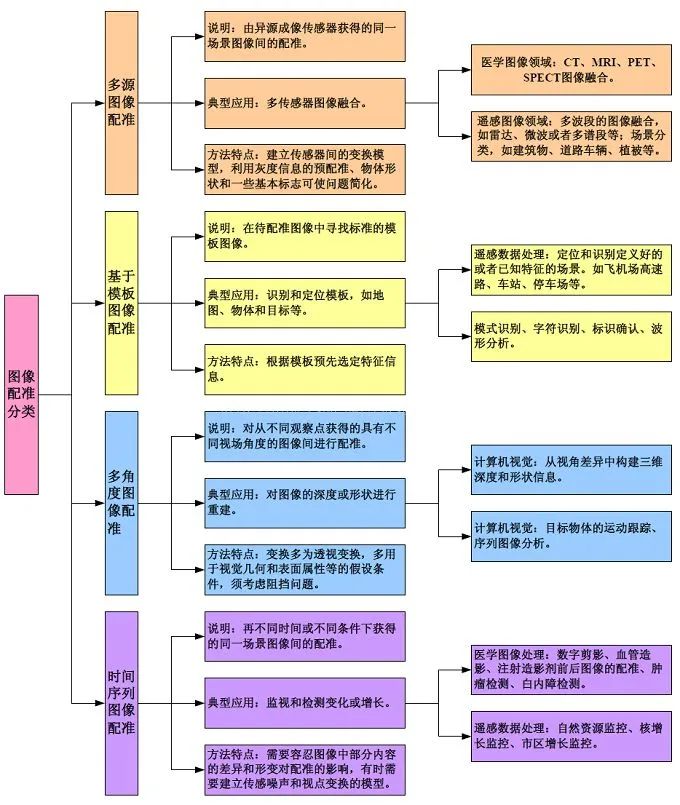

图像配准分类标准不唯一,下面两图是某位研究者的分类结果(2014年)。

笔者依照自己的理解做了如下的分类:

根据问题特点的分类: